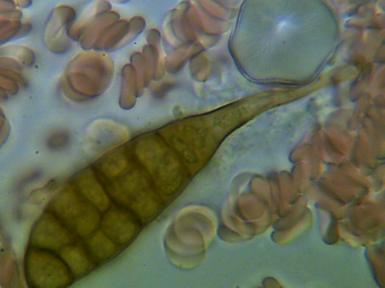

2.KRYSZTAŁY KWASÓW

Obecność kryształów soli kwasów w organizmie świadczy o jego zakwaszeniu. Sól może odkładać się w nerkach w postaci piasku lub kamieni , w stawach powodując stan zapalny i zwyrodnienia oraz w wielu innych narządach.

3.KRYSZTAŁY KWASU ORTOFOSFOROWEGO - którego obecność świadczy o zaburzeniu równowagi kwasowo-zasadowej. Wapń jest jednym z pierwiastków , które organizm wykorzystuje do przywrócenia tej równowagi . Jeżeli zakwaszenie jest duże powstają coraz większe kryształy , w konsekwencji mamy problemy z paznokciami, włosami , zębami oraz wzrasta zagrożenie osteoporozą.

W WYNIKU ZAKWASZENIA DOCHODZI DO WYTWORZENIA W ORGANIZMIE WIELU INNYCH FORM KRYSTALICZNYCH I NADMIERNEGO ROZMNAŻANIA ORGANIZMÓW PASOŻYTUJĄCYCH: